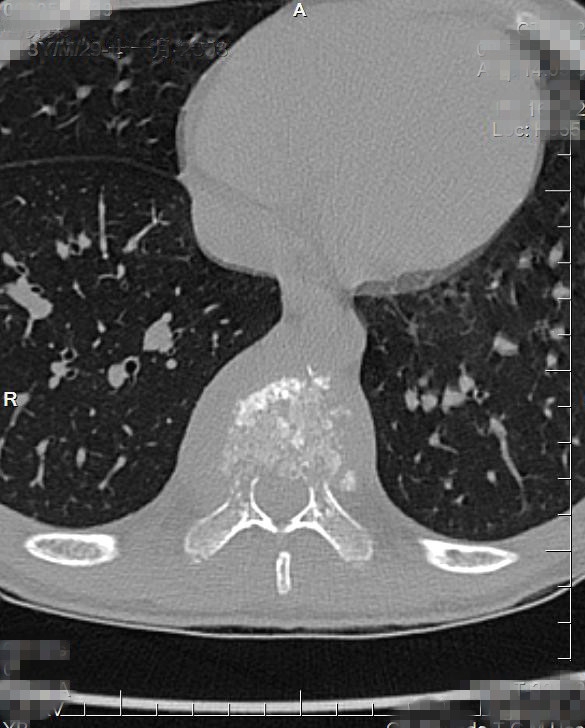

入院CT:结合MRI考虑,T9椎体病理性压缩性骨折,双侧椎弓根骨折,伴周围软组织感染性改变。

CT

椎体脊柱病变可单发或多发,椎体可呈楔形或完全变扁呈钱币状,亦可呈溶骨性破坏,很少累及相邻的椎体椎间隙。CT及MRI可多层面显示椎体及附件的溶骨性破坏椎体的溶骨性破坏。常累及一侧椎弓根,同时还可清楚显示椎旁的软组织肿胀和包块,亦可显示椎管内受累的情况。